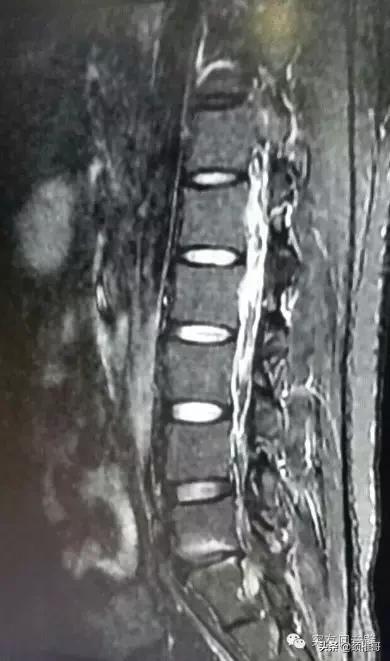

8月19日,我又去做了核磁检查,被诊断为“L5/S1椎间盘突出(左后型)、终板变性,左侧隐窝受压狭窄。L4/5、L5/S1椎间盘变性,L5/S1椎间隙缩窄”。到九月中旬(二次术后近五个月),臀部左侧至左脚踝间断性酸疼,走路超过一公里症状就会出现或加重。天晴时腰一点儿也不疼,但天气变化时腰部就会酸疼。晚上睡觉基本不受影响。

图3:2016年8月19日核磁影像资料